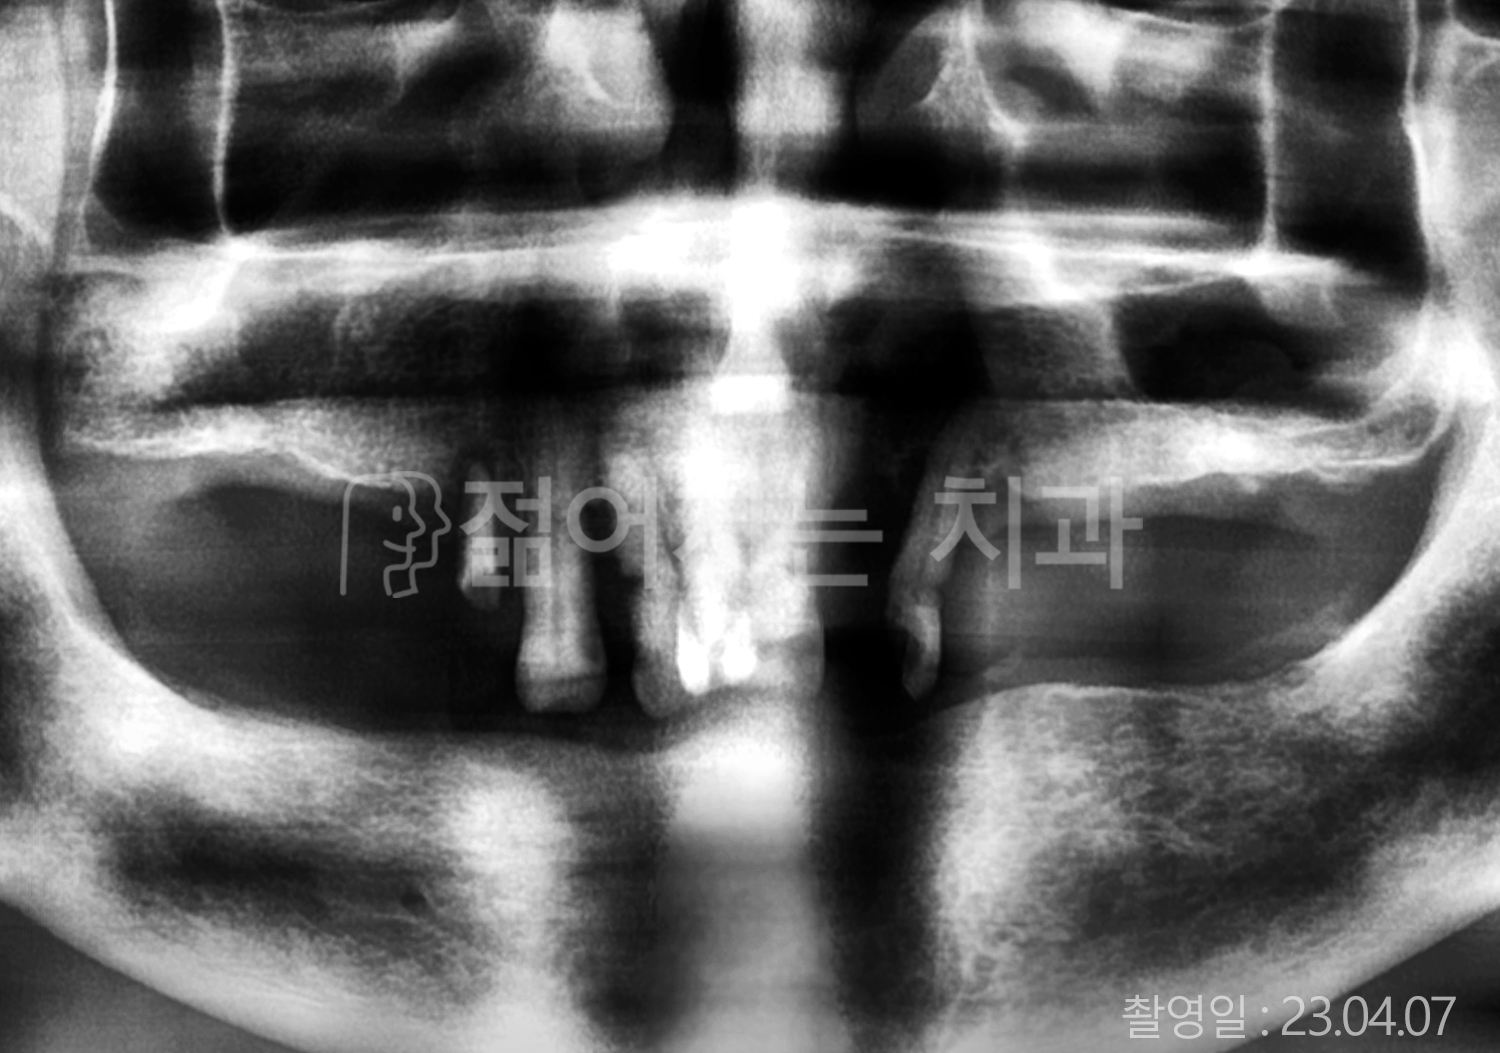

• 60대 고혈압, 고지혈증 전체치아 10개 이상 임플란트

• 70대 전체치아 10개 이상 임플란트

• 60대 전체치아 10개 이상 임플란트

• 50대 전체치아 10개 이상 임플란트

• 50대 고혈압, 고지혈증 전체치아 10개 이상 임플란트

• 60대 고혈압, 당뇨, 고지혈증 전체치아 10개 이상 임플란트

• 80대 고혈압, 당뇨, 골다공증 전체치아 10개 이상 임플란트

• 60대 고혈압 전체치아 10개 이상 임플란트

• 60대 고지혈증 전체치아 10개 이상 임플란트

• 60대 당뇨 전체치아 10개 이상 임플란트